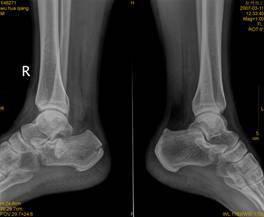

(图:罗大叔治疗后的双足X光)

第一个疗程治疗结束后,罗大叔的双足跖趾关节肿痛明显减轻,双足足跟肤色暗红消退,整个人精神状态也较之前大有改变。

第二个疗程治疗结束后,罗大叔的双足跖趾关节肿痛消失,双足踝关节红肿消退,双足足跟疼痛缓解,关节活动自如。

第三个疗程治疗结束后,罗大叔来院复查,双足痛风症状全部消失,关节活动自如,无任何不适,检查结果显示尿酸315μmol/L,在正常范围内,陈建春主任表示已临床康复标准。